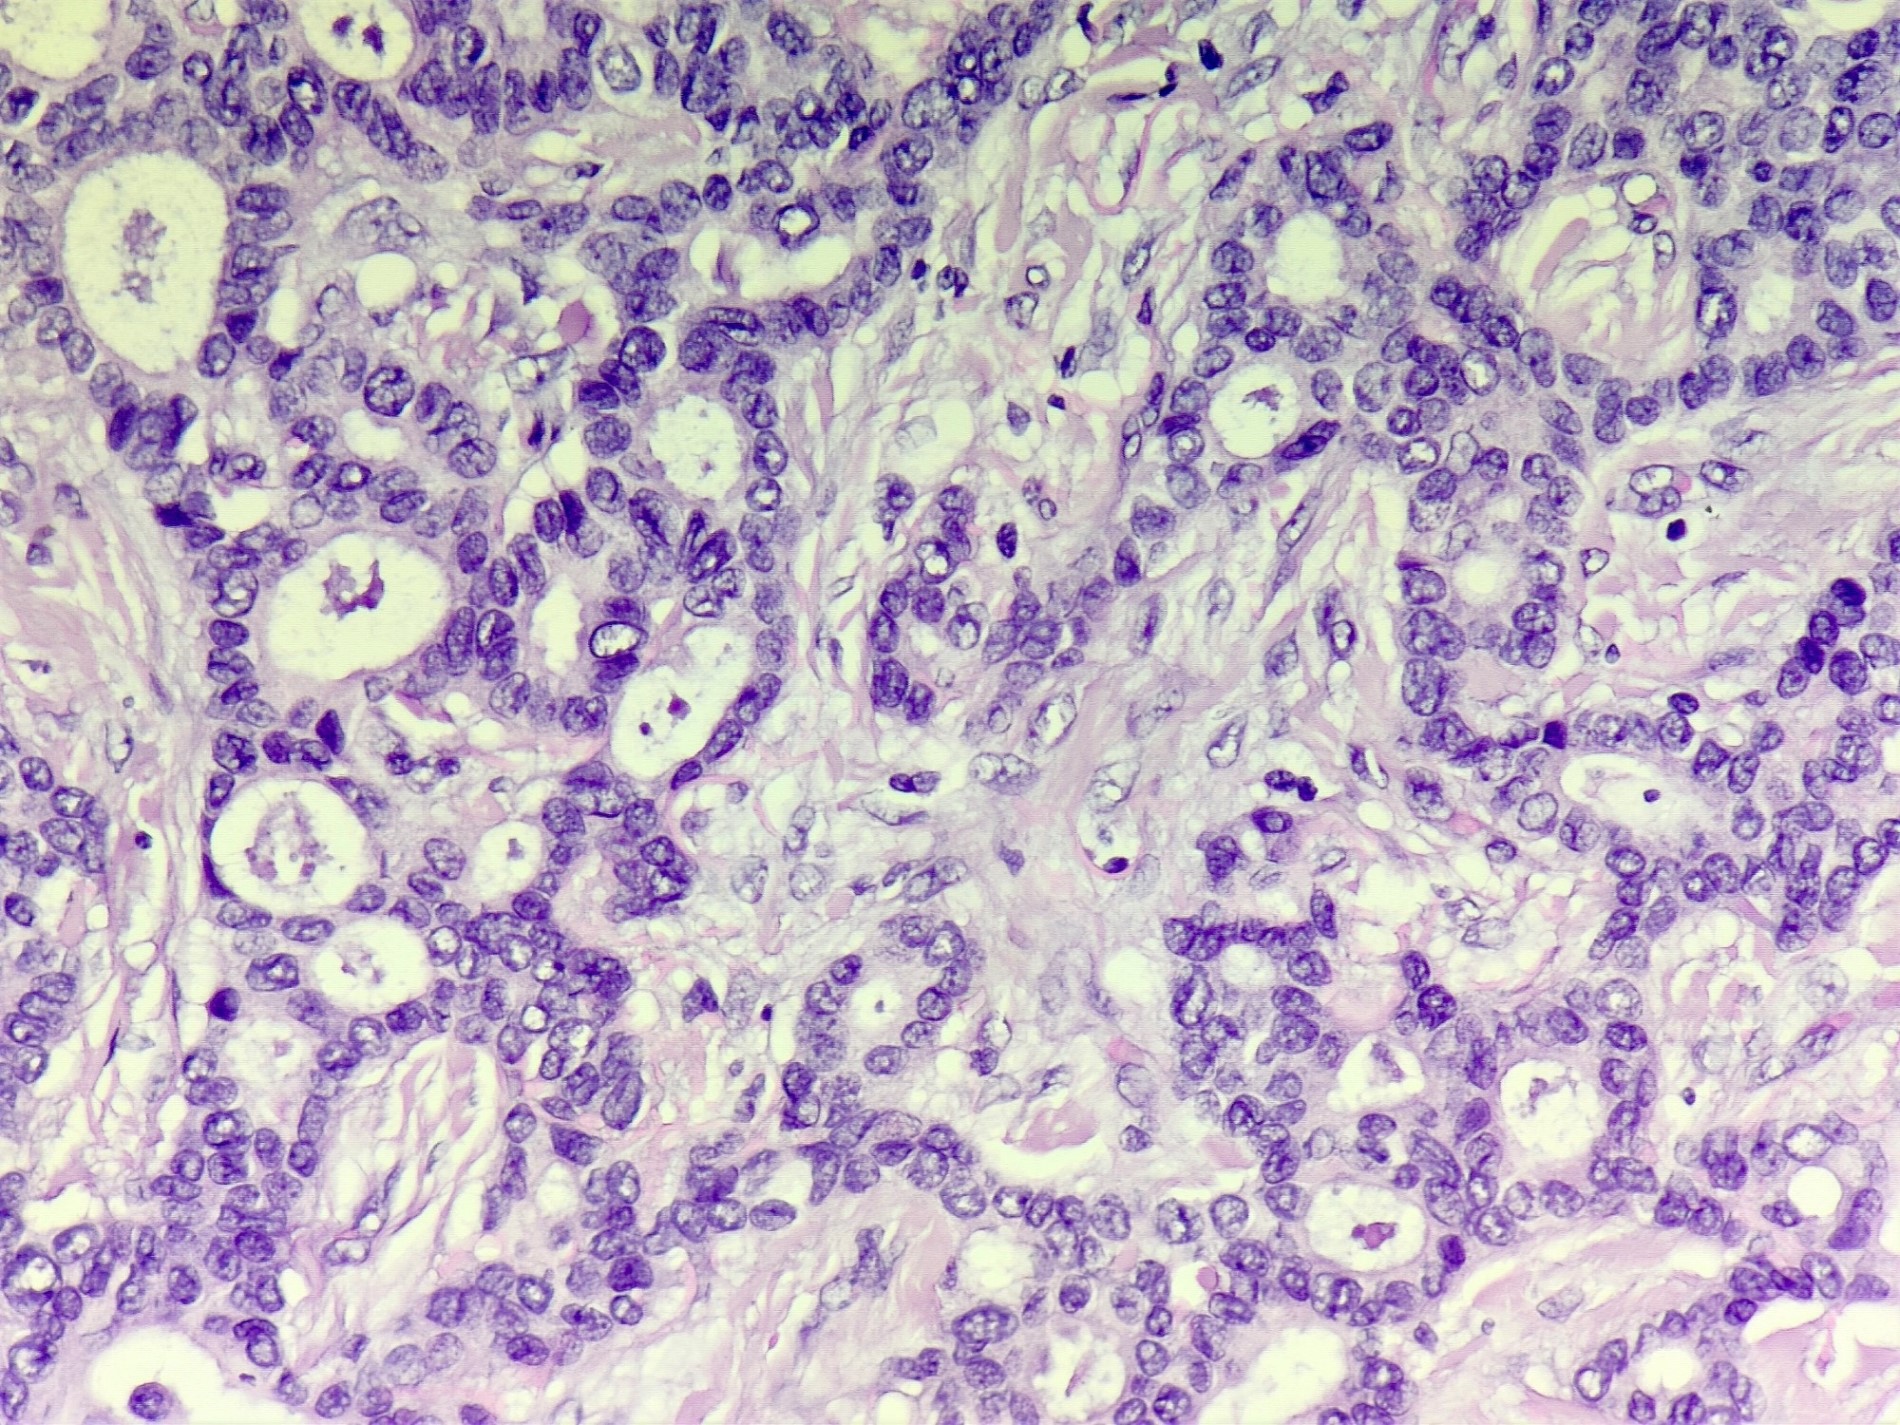

Microscopic (histologic) description

- Irregular cribriform growth pattern > 90% of cells

- Nuclear grade I pure ICC: > 90% cribriform pattern

- Mixed: 10 - 90% other morphological type, other than cribriform carcinoma

- Low grade: Nottingham grade 1 tumors

- Invasive islands or nests of malignant cells with round or angulated contours and well defined cribriform spaces formed by arches of epithelial cells; this gives a sieve-like appearance

- Tumor cells: small, mild / moderate pleomorphism, no nuclear atypia

- No / sparse mitotic activity

- Desmoplastic stroma

- Mucin positive secretion, microcalcifications in lumen

- Osteoclastic giant cells may be seen

- Myoepithelial cells absent

- Associated with cribriform ductal carcinoma in situ (DCIS)

Microscopic (histologic) images

Contributed by Sunitha Shankaralingappa, M.B.B.S, M.D., D.M.